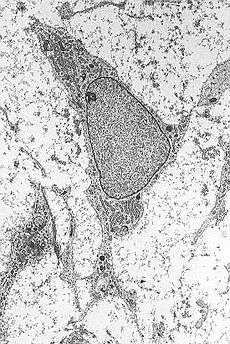

This "therapy", mainly aimed at neurodegenerative diseases, would rely on the conversion of mesenchymal stem cells into neurons[4] and it is currently kept secret by its promoters and lacking in scientific validation proving any therapeutic effectiveness;[5] it does not appear, moreover, that Vannoni ever published any article about Stamina therapy on scientific journals thus subjecting it to the usual peer review processes.[6]

The proposed method includes the conversion of mesenchymal stem cells (cells usually intended for generation of bones and adipose tissue) in neurons, after a short exposure to retinoic acid diluted in ethanol.[11] The therapy consists in removing cells from the bone marrow of patients, their in vitro manipulation (incubation of stem cells for 2 hours in an 18 micromolar solution of retinoic acid), and finally their infusion in patients themselves.[12]